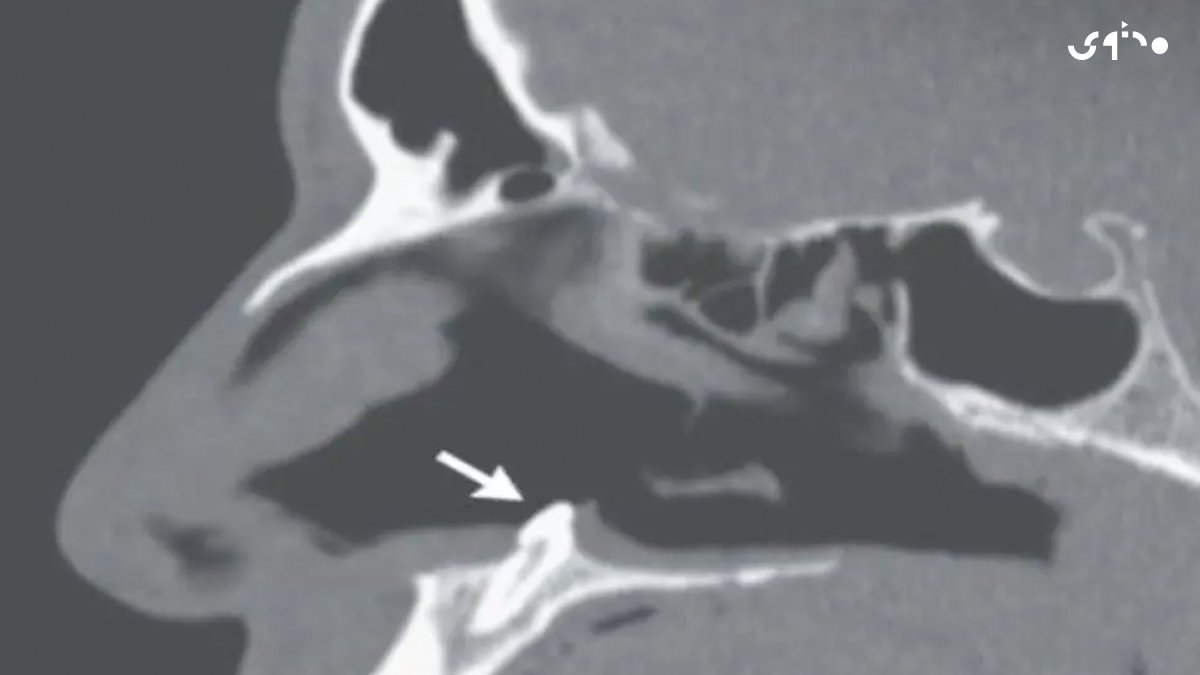

عانى شاب يبلغ من العمر 38 عاماً في نيويورك من انسداد بالمجرى التنفسي ليكشف التصوير المقطعي عن سن مقلوب في تجويف الأنف الأيمن يبلغ طوله 14 مليمتراً وعرضه 10 مليمترات وعلى الفور تمت إزالة السن جراحياً في مستشفى "ماونت سيناي"

تسمى هذه الحالة بـ"الأسنان المنتبذة" وفيها تبتعد الأسنان عن المسار المعتاد أثناء التكوين لتتواجد في أماكن لا يفترض أن تنمو داخلها وهي حالة نادرة للغاية لا تظهر سوى لدى حوالي 0.1% من الناس وهي أكثر شيوعاً لدى الرجال

تحدث هذه الحالة نتيجة الإصابة بصدمة أو كسر أو التهابات في منطقة الأنف وأيضاً جراء مشاكل وتشوهات في النمو كالشفة الأرنبية والحنك المشقوق ومن الممكن أن تتواجد نتيجة لعيب خلقي ولا تظهر إلا عند حدوث التهاب أنفي